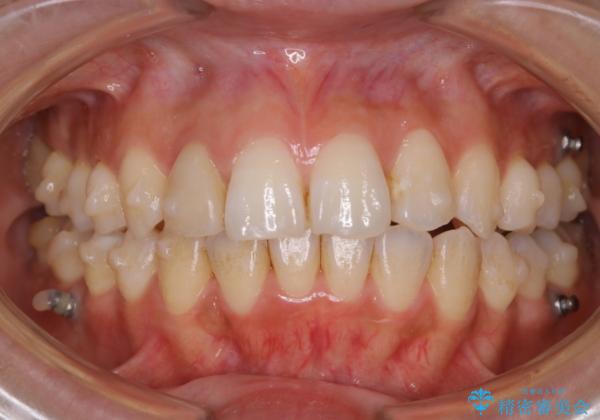

インビザラインの矯正中の方でアタッチメントが歯に付いているため、2ヶ月で着色やプラークが付いてきてしまいました。ホームケアや飲食の仕方により個人差はありますが、基本的には汚れが普段よりもつきやすいです。

定期的にクリーニングすることをおすすめします。